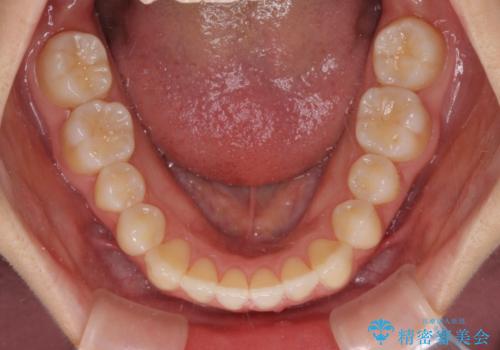

前歯のクロスバイト インビザラインによる矯正治療

- 前歯のクロスバイトを気にして来院された患者様です。

短期間での治療を希望され、ワイヤー装置とインビザラインとで悩んでいましたが、自己管理を徹底すると言うことでインビザラインによる矯正治療を行うこととしました。

しっかりとインビザラインの装着時間を守っていただいたので、1年弱で矯正治療を終えることができました。